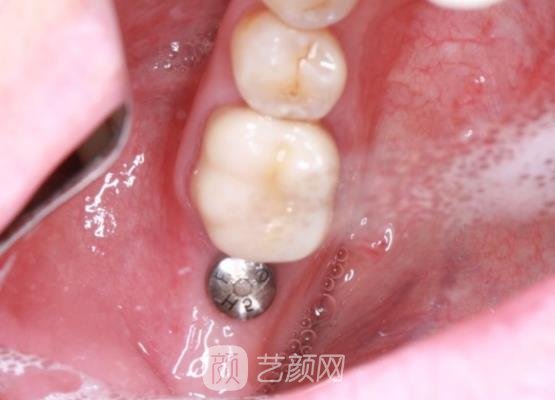

在确定进行种植牙之后,我也做了一些常规的检查,项目确定口腔没有医院敢在,操作过程当中都是在无菌室进行的,医生针对每一个细节都操作得很不错,结束调节之后也告诉我好好的做护理。

前两天去做了复查工作,医生说我恢复得很稳定,还为我佩戴了烤瓷牙冠。自从自己的牙齿变整齐之后,我感觉整个人也更加的开朗了,也越来越爱笑了,再也不像以前那样遮遮掩掩,因为微笑的时候很多人都说我的牙齿从外观上来看并没有什么异样感。